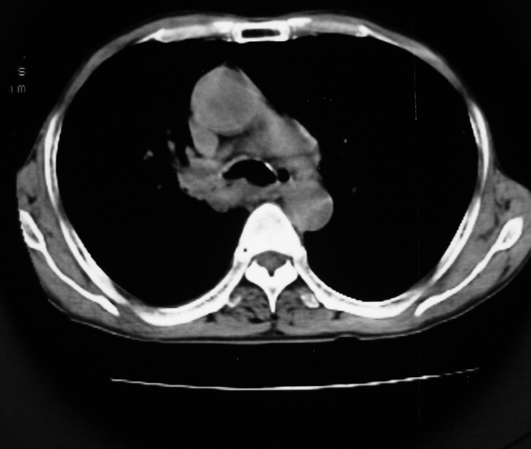

以下是引用同在2007-1-27 14:13:00的发言:[br]支持右侧中央型肺癌伴阻塞性病变.

以下是引用zjzjr在2007-1-27 16:56:00的发言:[br]支持右肺中心型肺癌伴阻塞性肺炎.